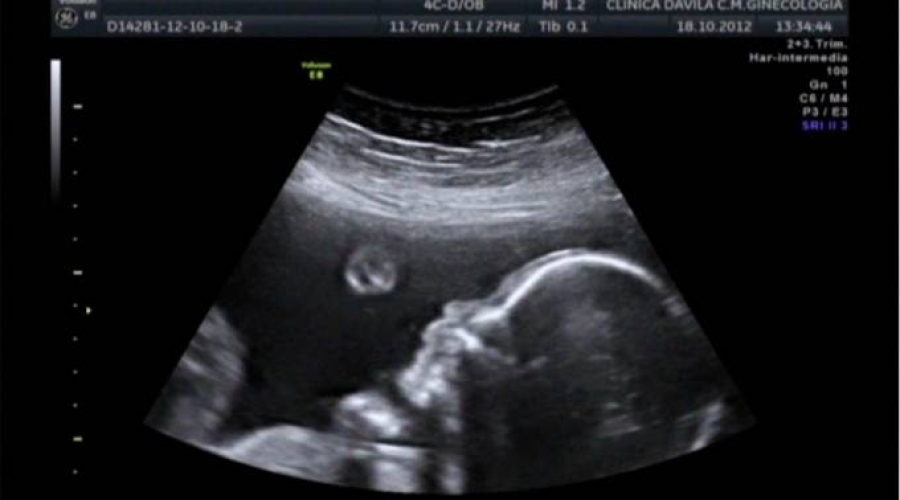

Los científicos hicieron el experimento con 39 bebés no nacidos que estaban en el tercer trimestre de gestación utilizando la tecnología ultrasonido 4D. Proyectaron sobre el vientre de las embarazadas imágenes similares a un rostro humano. Estas estaban compuestas por tres puntos que formaban una pirámide invertida y que correspondían con la posición de los ojos y la boca. También proyectaron imágenes con tres puntos en forma de pirámide. Se descubrió que los bebés giraban la cabeza y miraban durante más tiempo a las proyecciones de la pirámide invertida.